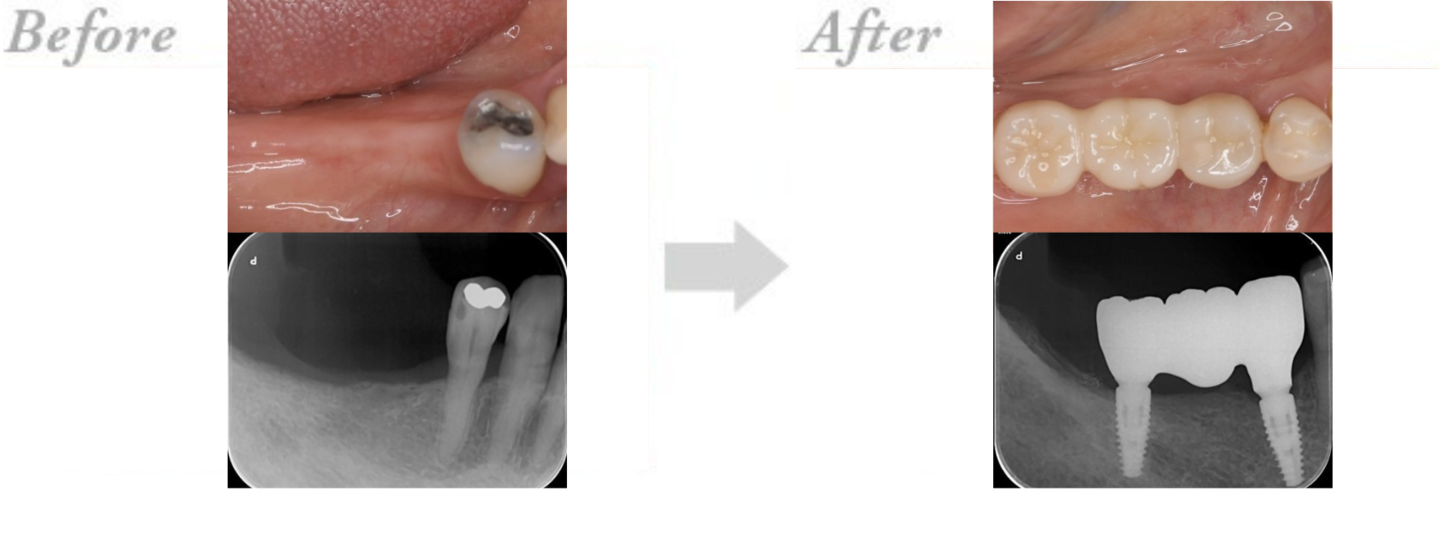

◆インプラント治療の実例 CASE3